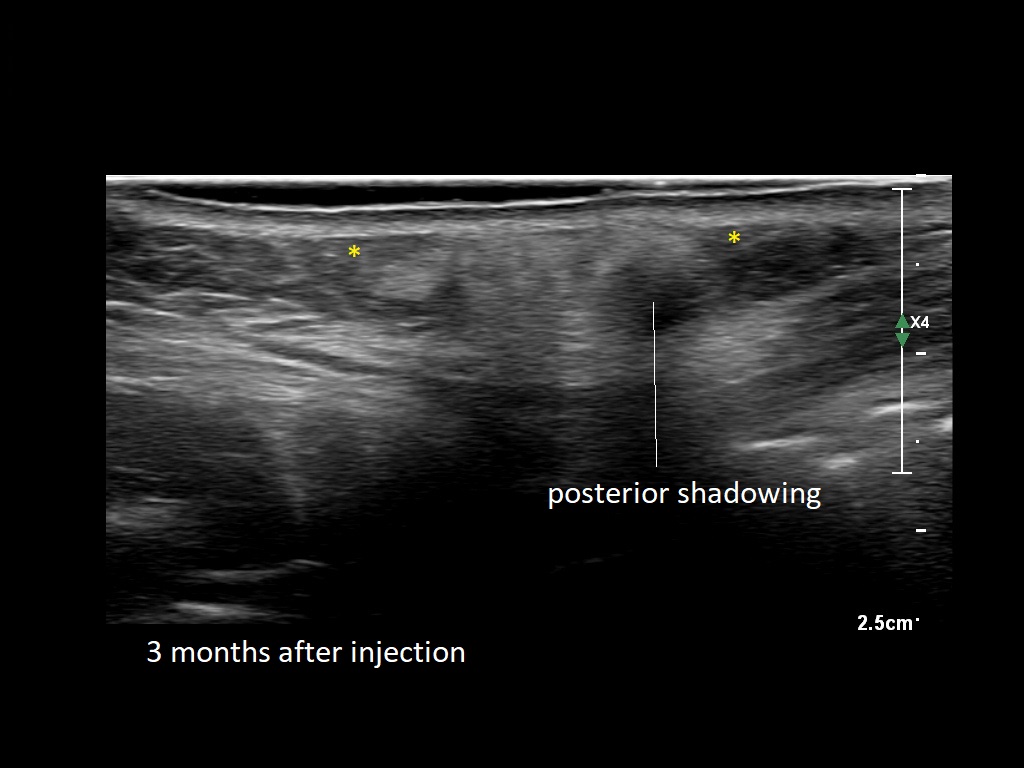

Draw in the second image below where the fillers are located. To check if your answer is correct, swipe the first image to the right.